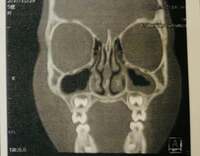

この日は「大きな病院でCT検査をしたら、、、なんと両方の肺に肺炎 さらに慢性の副鼻腔炎だと言うことが判明しました」と検査結果を報告。「鼻の骨が曲がっている事も判明」したといい「まだ子供なので元々狭い鼻腔が粘膜の腫れでさらに狭くなるため鼻づまりの症状が悪化し、慢性副鼻腔炎になっていたみたいです」と説明した。

続けて「前に違う病院でレントゲンを撮った時には肺炎や副鼻腔炎は見られなかった」と述べつつ、医師からは「5歳児の未熟な体や小さな肺炎はレントゲンに映らない場合もあったりして中々見つけるのが難しい」と言われたそうで「咳の原因はおそらく肺炎もしくは副鼻腔炎だろう」と診断されたことを明かした。